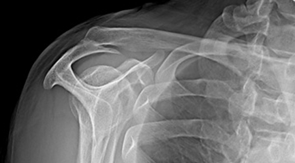

충돌증후군 수술 전 사진